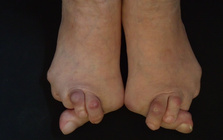

靴の害、外反母趾

靴の健康被害、外反母趾。

外反母趾の問題は痛みだけではありません。

その変形症状から多くの身体の不具合と

Hallux valgus